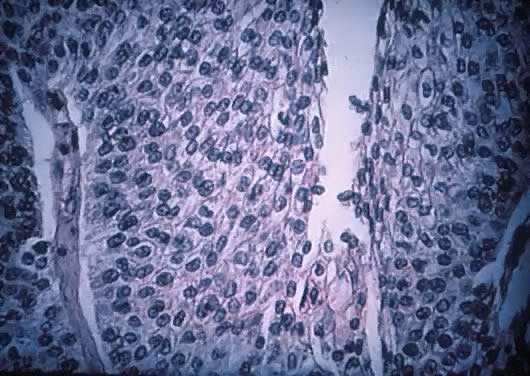

Microscopically, the tumors exhibited fine, elongated branching papillae supported by delicate fibrovascular cores (Figs. 18 and 19). In some cases, the stroma is broad and edematous. The papillae are similar to those of the serous tumors. The lining epithelium is tall columnar with a basally located nucleus. These tumors are lined mostly with endocervical-type epithelium. The cell cytoplasm is basophilic. The cells could be stratified up to 20 layers, usually present at the tip of the papillae. These peculiar epithelial “nests” are observed in most of the tumors of this type, invalidating the criterion of three layers, which generally is accepted as a dividing line between LMP mucinous tumors and cystadenocarcinoma (see the section on intestinal-type mucinous ovarian tumors of LMP later). Tufting is present, similar to that seen with the serous tumors. Epithelium forming a filigree pattern is a common finding (see Fig. 19), and occasionally a few ciliated cells are observed.

Fig. 18. Mucinous cystadenoma of low malignant potential, endocervical or müllerian type. Observe the marked papillation similar to that seen in serous tumors. Tufting and inflammatory exudate in the cyst lumen are seen (hematoxylin and eosin, 212). Inset, upper left. Papillation and inflammatory exudate. Inset, lower right. Epithelial atypia of gland-like spaces (420).

Fig. 19. Mucinous cystadenoma of low malignant potential, endocervical type, exhibiting a filigree pattern, pluristratification with atypia, stroma with mucinous material and inflammatory cell infiltration at the upper right-hand corner, and cellular debris with inflammatory cell exudate in the lumen (hematoxylin and eosin, 520).

Nuclear atypia is present, varying from mild to severe. Polymorphonuclear leukocytes often are found in the stroma, epithelium, and in the cyst lumen, intermingling with plasmalymphocytic infiltrates. Occasionally, multinucleated cells of foreign body type are seen in the tumor, presumably in response to mucus infiltration of the intramural stroma. The surface of the ovary is involved by tumor in 13% of the cases of endocervical type, compared with 6% of tumors of the intestinal epithelial type.